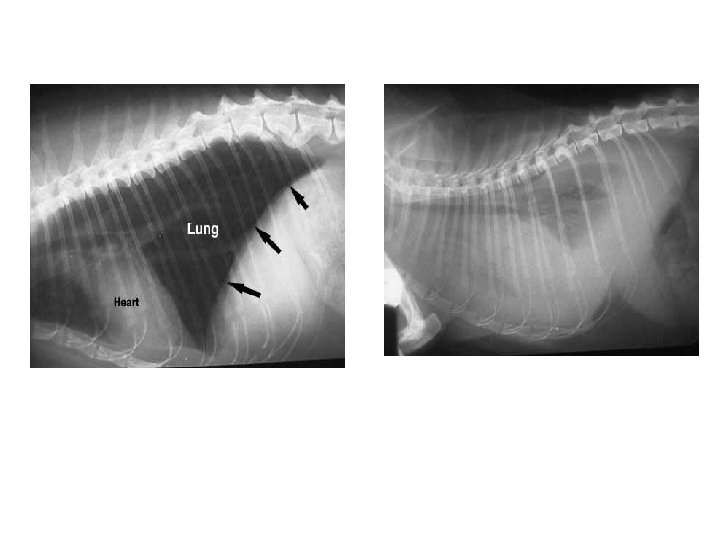

This is an x-ray of a normal cats thorax. This cat is laying on its right side, the head is towards the left. You can see the heart and the black lung tissue in the shape of a triangle. The diaphragm (arrows) is the vertical line that separates the thorax on the left from the abdomen on the right. The liver resides in the abdomen.

This cat has a significant amount of fluid in the thorax (pleural effusion), making it difficult to identify normal organs. You cannot see the heart or diaphragm, and the lung tissue is greatly reduced because of all the fluid. The lungs are unable to expand fully causing significant difficulty in breathing. This pet is very ill and has minimal breathing reserve. It needs immediate removal of the fluid.

After some of the fluid was removed it is possible to visualize more of the organs. There is more lung tissue present and the top of the diaphragm is now visible.